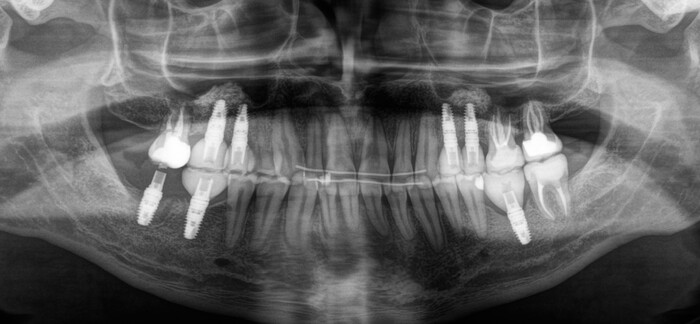

Коронок на рентгеновском снимке вы не увидите, потому что пластик не рентгеноконтрастен. Видны лишь металлические абатменты, за которые «держится» пластмассовая часть, – такие палки-переходники между имплантатом и коронкой. Временные коронки изготовлены из фрезерованной пластмассы. Пластмассовый брусок выпиливается в специальном станке и на выходе представляет собой практически готовую коронку.

В полости рта это выглядит так:

Я решил добавить фотографии сразу после снятия брекетов, а не с ними, как это было на рентгеновском снимке. Думаю, так выглядит намного симпатичнее.

Коронки страшненькие – на то они и временные. Такой тип коронок необходим для «доформирования контура десны» и для того, чтобы «ввести области в жевание» из-за длительного отсутствия зубов. Необходимо подготовить мышцы, связки, сустав, остальные зубы к нормальному жеванию. Временные коронки можно корректировать при необходимости.

Шло время. Так же молниеносно, как проходит молодость. Ещё 3 месяца и пора менять временные коронки на постоянные. Кстати, средний срок использования временных конструкций как раз 3-4 месяца. Почему? Как минимум, пластик истирается, как максимум, очень хорошо задерживает на себе еду и зубной налёт, что при хреновом уходе приводит к воспалению и проблемам.

В процессе лечения 7-ой зуб на нижней челюсти треснул, появился скол, пришлось от него тоже избавиться. Ниже снимок с постоянными коронками и «внеплановым» имлпантатом:

Коронки на этом снимке уже четко различимы, потому что сделаны из керамики.

Вид «изнутри»:

Ещё один квантовый скачок и проходит 3.5 месяца. Выход на сцену временной коронки на имплантате, который был установлен позже остальных:

Вы её видите? И я не вижу. А она есть: